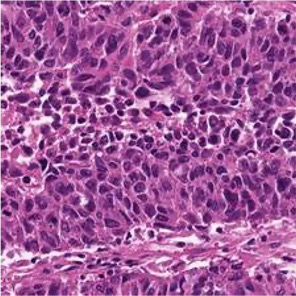

Multiple instance learning (MIL) is a powerful approach to classify whole slide images (WSIs) for diagnostic pathology. A fundamental challenge of MIL on WSI classification is to discover the \textit{critical instances} that trigger the bag label. However, previous methods are primarily designed under the independent and identical distribution hypothesis (\textit{i.i.d}), ignoring either the correlations between instances or heterogeneity of tumours. In this paper, we propose a novel multiplex-detection-based multiple instance learning (MDMIL) to tackle the issues above. Specifically, MDMIL is constructed by the internal query generation module (IQGM) and the multiplex detection module (MDM) and assisted by the memory-based contrastive loss during training. Firstly, IQGM gives the probability of instances and generates the internal query (IQ) for the subsequent MDM by aggregating highly reliable features after the distribution analysis. Secondly, the multiplex-detection cross-attention (MDCA) and multi-head self-attention (MHSA) in MDM cooperate to generate the final representations for the WSI. In this process, the IQ and trainable variational query (VQ) successfully build up the connections between instances and significantly improve the model's robustness toward heterogeneous tumours. At last, to further enforce constraints in the feature space and stabilize the training process, we adopt a memory-based contrastive loss, which is practicable for WSI classification even with a single sample as input in each iteration. We conduct experiments on three computational pathology datasets, e.g., CAMELYON16, TCGA-NSCLC, and TCGA-RCC datasets. The superior accuracy and AUC demonstrate the superiority of our proposed MDMIL over other state-of-the-art methods.